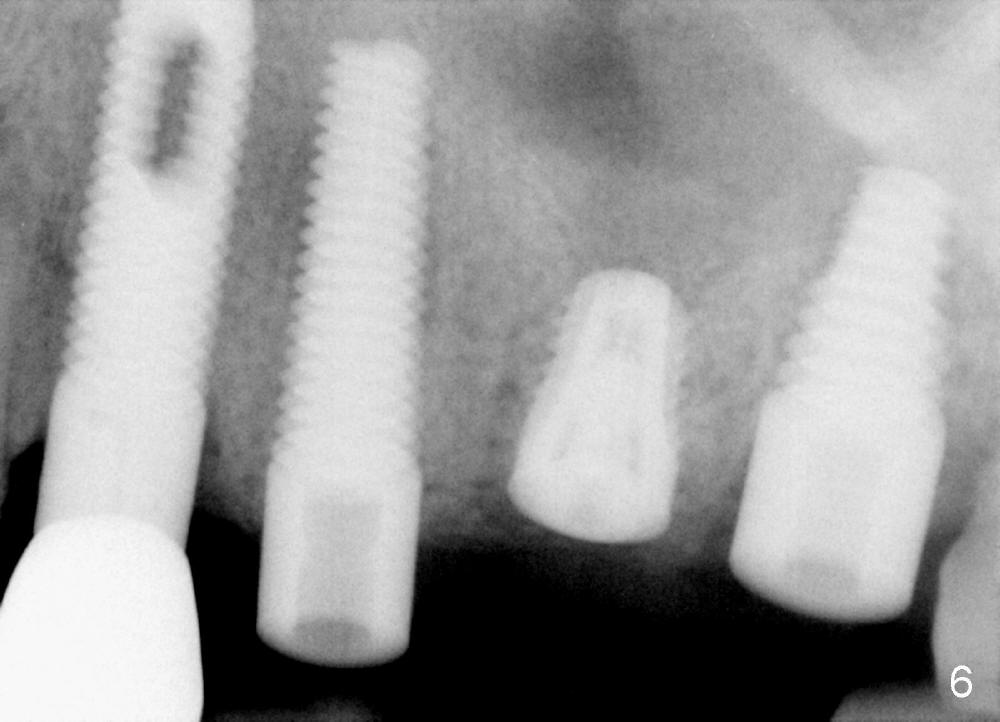

A 84-year-old man has a failing bridge.  A short implant was placed at the pontic site 5 months ago (Fig.1, taken 2 months postop).  The bridge was temporarily recemented.  It is planned at next appointment to extract #13, uncover the implant at pontic and save #15 if possible.  When the bridge is removed, the tooth #15 is also found non salvageable (Fig.2). The root stump of #15 is oval, 5x10 mm.  Preop PA shows that the 2nd molar has two roots (Fig.1: *).  When the tooth is extracted, the septum is found wide buccolingually (Fig.3: S, between the buccal (B) and palatal (P) sockets).  Osteotomy is formed in the septum with combination of drills and osteotomes, followed by insertion of taps (Fig.4).  Finally the osteotomy (Fig.5 O) in the septum (S) of #15 deviates into the buccal (B) socket.  When the implant is placed (Fig.6), it deviates buccally slightly (Fig.7).  The remaining sockets are filled by bone graft (Fig.7 G).  Immediate provisional bridge is fabricated after placement of abutments (A).  The main purpose of the provisional at early stage is to hold bone graft in place.  There is no occlusal contact with the opposing dentition,  Due to time constraint, the uncovering of #14 is postponed.  The provisional dislodges 2-3 days postop.  The patient returns for recementation 5 days postop; the sockets have initially healed (Fig.8,9, as compared to Fig.7).